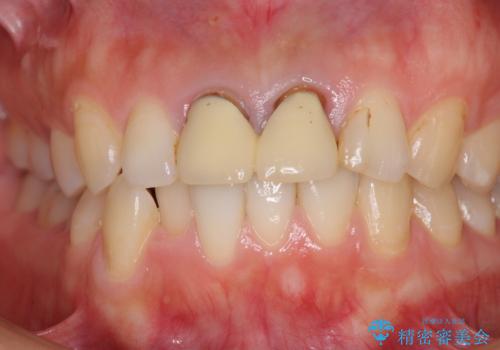

- 前歯のクラウンが着色により不自然な色となっていることを気にして来院された患者様です。

クラウンと歯の縁も合っておらず、汚れが溜まりやすい環境であったため、前歯2歯のクラウンをオールセラミッククラウンにて再補綴することとしました。